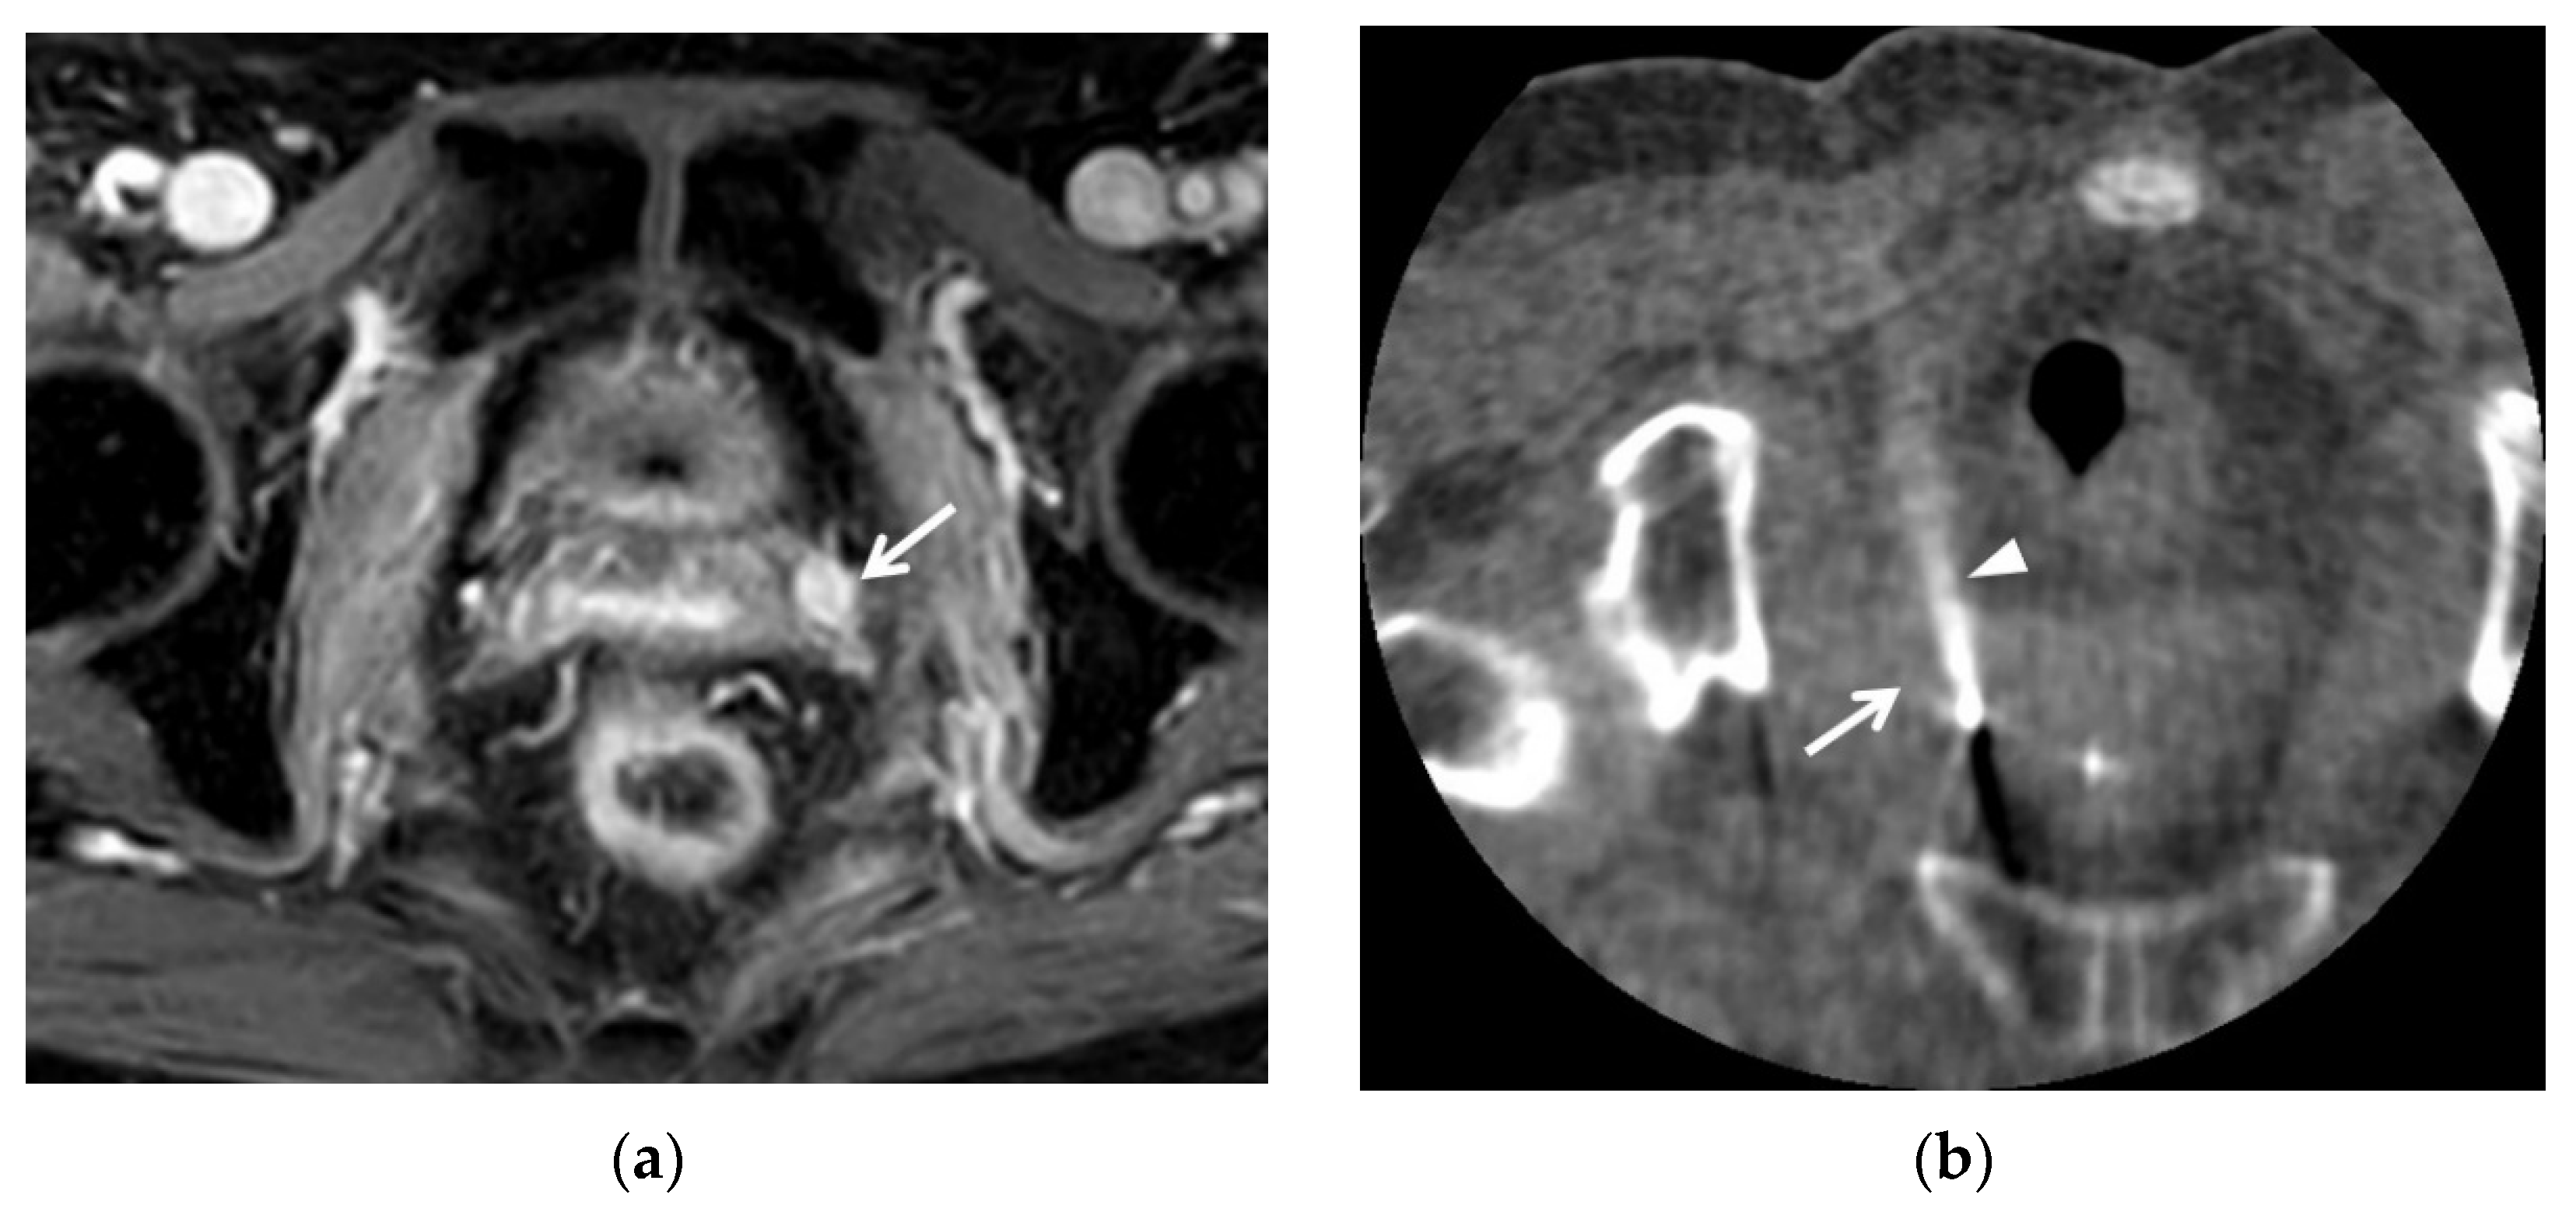

3.1. T2WI Findings

3.2. T1WI Findings